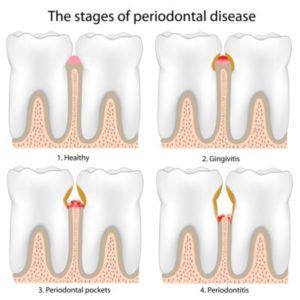

Signs & Symptoms of Periodontal Disease

Periodontal disease – also known as gingivitis and periodontitis – is most easily identified by the visible symptoms it causes as it progresses. In its beginning stages, a periodontal disease often causes no symptoms at all, making it difficult for the average person to notice. With time, bacteria begin causing inflammation in the gums, which […]

Periodontal scaling and root planing are procedures used to treat periodontal disease. Thought of by many as a ‘deep cleaning’, this in-office procedure involves the careful removal of hardened plaque near the gum line, where harmful bacteria can grow and cause damage to both the hard and soft tissues of the mouth. The treatment starts […]